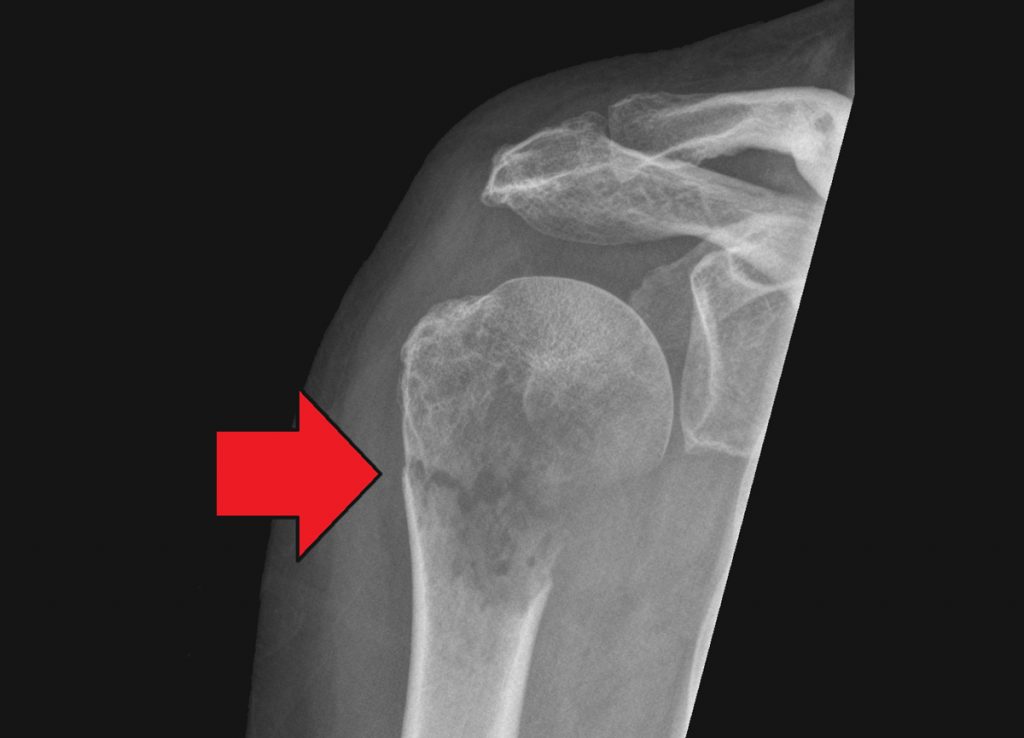

Las localizaciones más comunes son los huesos largos (fémur, húmero), las vértebras y las costillas, aunque cualquier hueso puede verse afectado dependiendo de la enfermedad causante.

- Radiografía: puede mostrar lesiones líticas (destructivas), escleróticas (densas) o mixtas.

- Tomografía computarizada (TC) o resonancia magnética (RM): para evaluar la extensión del daño óseo y de tejidos blandos.